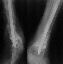

Здравствуйте, коллеги!!! К нам в отделение госпитализирован пациент 39 лет с клинико-рентгенологической картиной ложного сустава в/3 плечевой кости! Снимки прилагаются! Предистория такова: около года назад получил оскольчатый перелом в/3 плечевой кости. В одной из московских больниц выполнен остеосинтез пластиной, через несколько месяцев выполнен реостеосинтез, опять же пластной...., причины реостеосинтеза со слов пациента таковы - "доктору не понравилась как лежит пластина и он ее переложил..." - два месяца назад выполнено удаление фиксатора. Никаких выписок у больного нет. Около недели назад больной ударился областью плечевого сустава, появились боли, в связи с чем он обратился в травмопункт, откуда направлен к нам. Клинически у пациента имеется подвижность в области в\3 плеча, костная крепитация, умеренная болезненность в в/3 плеча при движениях, атрофия дельтовидной мышцы. На следующей недели планируем пациента опериравать. Коллеги, у нас возникло несколько вопросов, если не затруднит, то посоветуйте и подскажите... Мы планируем выполнить закрытый блокируемый остеосинтез, скажите пожалуйста, нужно ли в этом случае, на ваш взгляд, выполнять костную пластику или достаточно выполнить рассверливание костномозгового канала и заштифтовать толстым гвоздем, нужно ли пытаться удалить винты??? У нас в отделении идут дискуссии по этому поводу, придти к общему знаменателю не можем, поэтому и обращаемся к Вам!!! На основании ваших отзывов мы и примем окончательное решение!!! Спасибо!!! Очень ждем Ваших комментариев!!!

1. жизнеспособность головки плечевой кости, которая может быть установлена при КТ плечевого сустава. Если головка нежизнеспособная, то единственной альтернативой артродезу в данном случае является онкологический плечевой протез

2. характер ложного сустава и состояние костных отломков: четкая рентгенологическая картина гипотрофического (аваскулярного) ложного сустава с выраженным склерозом концов отломков и значительным дефектом костной ткани диктует необходимость введения в область ложного сустава остеоиндутивного материала (если бы не было значительного дефекта и склероза концов отломков в межотломковую область можно было бы ввести костную крошку, полученную при рассверливании костномозгового канала). В данном случае значительный дефект кости и плохое состояние концов требует: а)«освежения концов отломков», б) введения в область ложного сустава васкуляризированого костного трансплантатата, либо свободного костного аутоторансплантата, либо выполнение дистракционного остеосинтеза («костного транспорта»). При этом Вам естественно придется «открывать» область перелома, а значит Вы легко удалите винты.

3. состояние костной ткани поврежденного сегмента: в данном случае костная ткань остеопорозна, с многочисленными «дырами» от винтов, ранее фиксировавших пластины. Поэтому фиксировать пластиной третий раза нецелесообразно. Остаются 2 метода: блокированный штифт для проксимального плеча (Т2 страйкер или аналоги), либо аппарат внешней фиксации (чем лучше владеете).

Провести штифт в дистальный отломок закрыто вряд ли удастся: «сосулькообразный» конец отломка, запаянный костномозговой канал, дополнительное препятствие в виде 2 винтов.